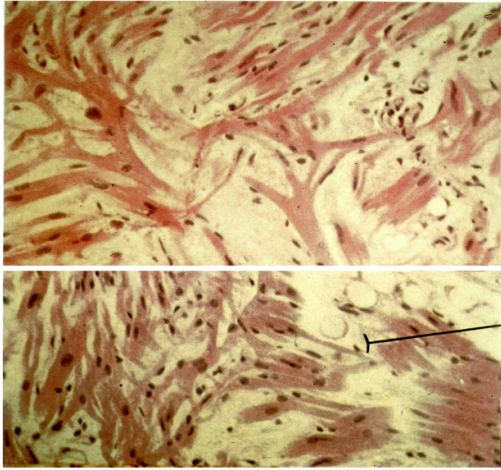

ID